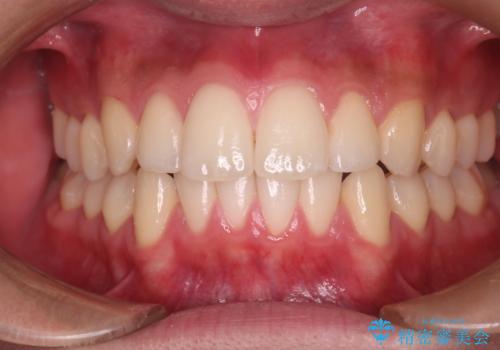

【審美ワイヤー】八重歯とがたつき気になる